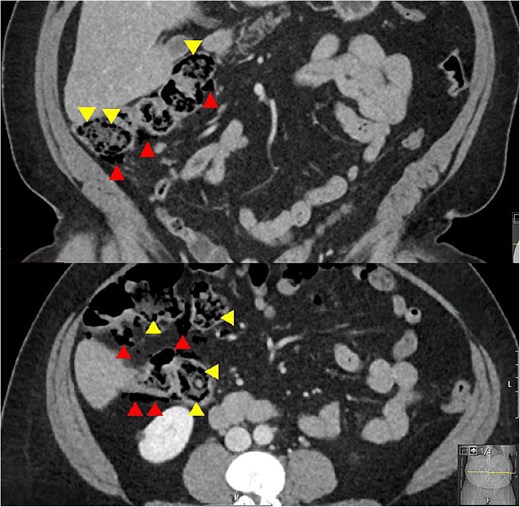

A woman in her 50s presented to the Emergency Department with a 1-week history of worsening right sided abdominal pain. Background included chronic back pain managed with long term methadone 100 mg once daily, and previous hepatitis C treated 9 years earlier with pegylated interferon and ribavirin. There was no history of vascular disease. She was taking lactulose 50 mL once daily to treat constipation secondary to methadone and described longstanding issues with abdominal discomfort, bloating, and frequent flatulence. She was living independently with her family, was an ex-smoker and previous IV drug user. On examination she was in some distress. Her vital signs were all normal. Abdominal examination revealed peritonism in the right abdomen. Blood tests showed normal inflammatory markers with a white cell count of 6.2 × 109/L, neutrophils of 2.8 × 109/L, and a C-reactive protein (CRP) of 6 mg/L. A CT abdomen was performed and was reported to show free air, which on review showed multiple subserosal and submucosal locules of air in the caecum and ascending colon, and a small volume of intra-abdominal free air with no free fluid. There were no other features to suggest ischaemia and no colonic diverticulosis (Fig. 1).

Coronal and axial CT slices showing pneumatosis in the right colon. Arrowheads demonstrate subserosal and submucosal gas.

The main differential diagnosis was between an acute abdomen with ischaemia of the right colon versus PC secondary to high dose lactulose. The degree of pain, patient distress, and localized peritonism with free air in the peritoneal cavity and air in the wall of the right colon was consistent with an acute abdomen. However, the normal vital signs and CRP of 6 mg/L suggested otherwise. The background of high dose lactulose, abdominal bloating and increased flatus, combined with the pattern of submucosal and subserosal air led to a provisional diagnosis of PC secondary to high dose lactulose being made. This resulted in a trial of medical treatment and avoidance of an acute laparoscopy or laparotomy.